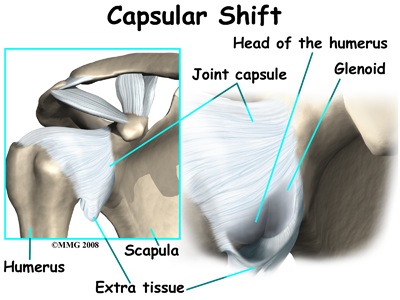

Capsular Shift

Another surgery to tighten a loose shoulder joint is a procedure called a capsular shift. The lining of any joint is called the joint capsule. The joint capsule forms a pocket, or bag that is made up of the ligaments and connective tissue around the joint. The shoulder joint has a fairly large joint capsule that is necessary to allow the joint to move in such a wide range.

Sometimes the problem causing the shoulder instability is because the joint capsule is simply too large. This is sometimes referred to as a redundant, or patulous joint capsule. This may cause shoulder instability in multiple directions. This is sometimes referred to as multi-directional instability. In order to fix this type of instability, the joint capsule needs to be made smaller and tightened.

This procedure also can be performed using the arthroscope. The surgeon pulls the flap of tissue over the front of the capsule and connects it together. This is similar to when a tailor tucks loose fabric by overlapping and sewing the two parts together. Once the appropriate degree of tightness is achieved, the surgeon uses a combination of sutures and suture anchors to hold the joint capsule in this position until healing occurs.